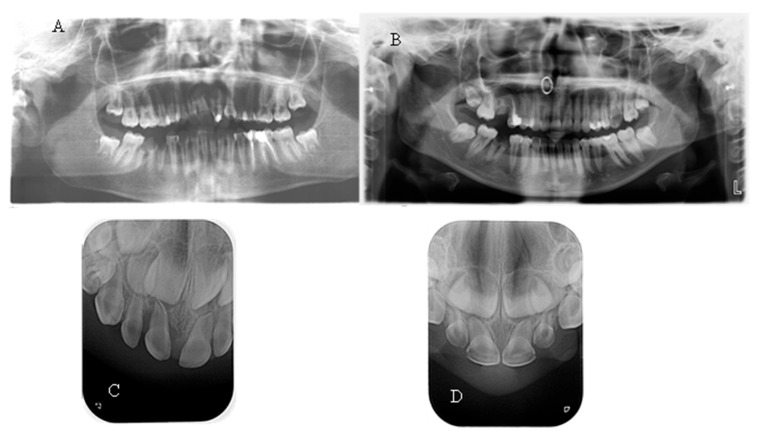

X-linked hypophosphatemic rickets (XLH) is a rare genetic disorder with a frequency of 1:20,000, caused by mutations in the PHEX gene, resulting in impaired phosphate metabolism and bone mineralization. There is an association between hypophosphatemia and dental issues, though this link is not definitively established. This study aims to evaluate the dental status, including oral hygiene, caries prevalence, and malocclusions, as well as parental awareness of dental complications, in children with XLH in Bulgaria, particularly those receiving or about to begin burosumab treatment, and to compare their oral health status with that of healthy children. Eleven children with XLH (seven girls, four boys, aged 2.5-17 years), nine receiving burosumab, were assessed and compared with eleven age- and gender-matched healthy children (seven girls, four boys, aged 2.5-17 years) without XLH or systemic conditions affecting dental health. Parental awareness of dental implications was assessed via a questionnaire, revealing no awareness of potential complications. Oral hygiene, measured using the Oral Hygiene Index-Simplified (OHI-s), was poor in 66.67% of children, with an average of 6.45 ± 5.80 carious lesions per child, and was highest in the 11-16 age group. Malocclusions were observed in 63.64% of children, and spontaneous endodontic infections occurred in 18.18%. Compared with healthy children, patients with XLH had significantly worse oral hygiene (p = 0.013) and a higher caries prevalence (p = 0.001). Children with XLH exhibit poor oral hygiene, a high caries burden, and frequent malocclusions, compounded by a lack of parental awareness of dental risks. These findings underscore the need for targeted dental interventions and education in XLH management, including the integration of routine dental assessments and structured parental education programs into existing clinical protocols to improve oral health outcomes.